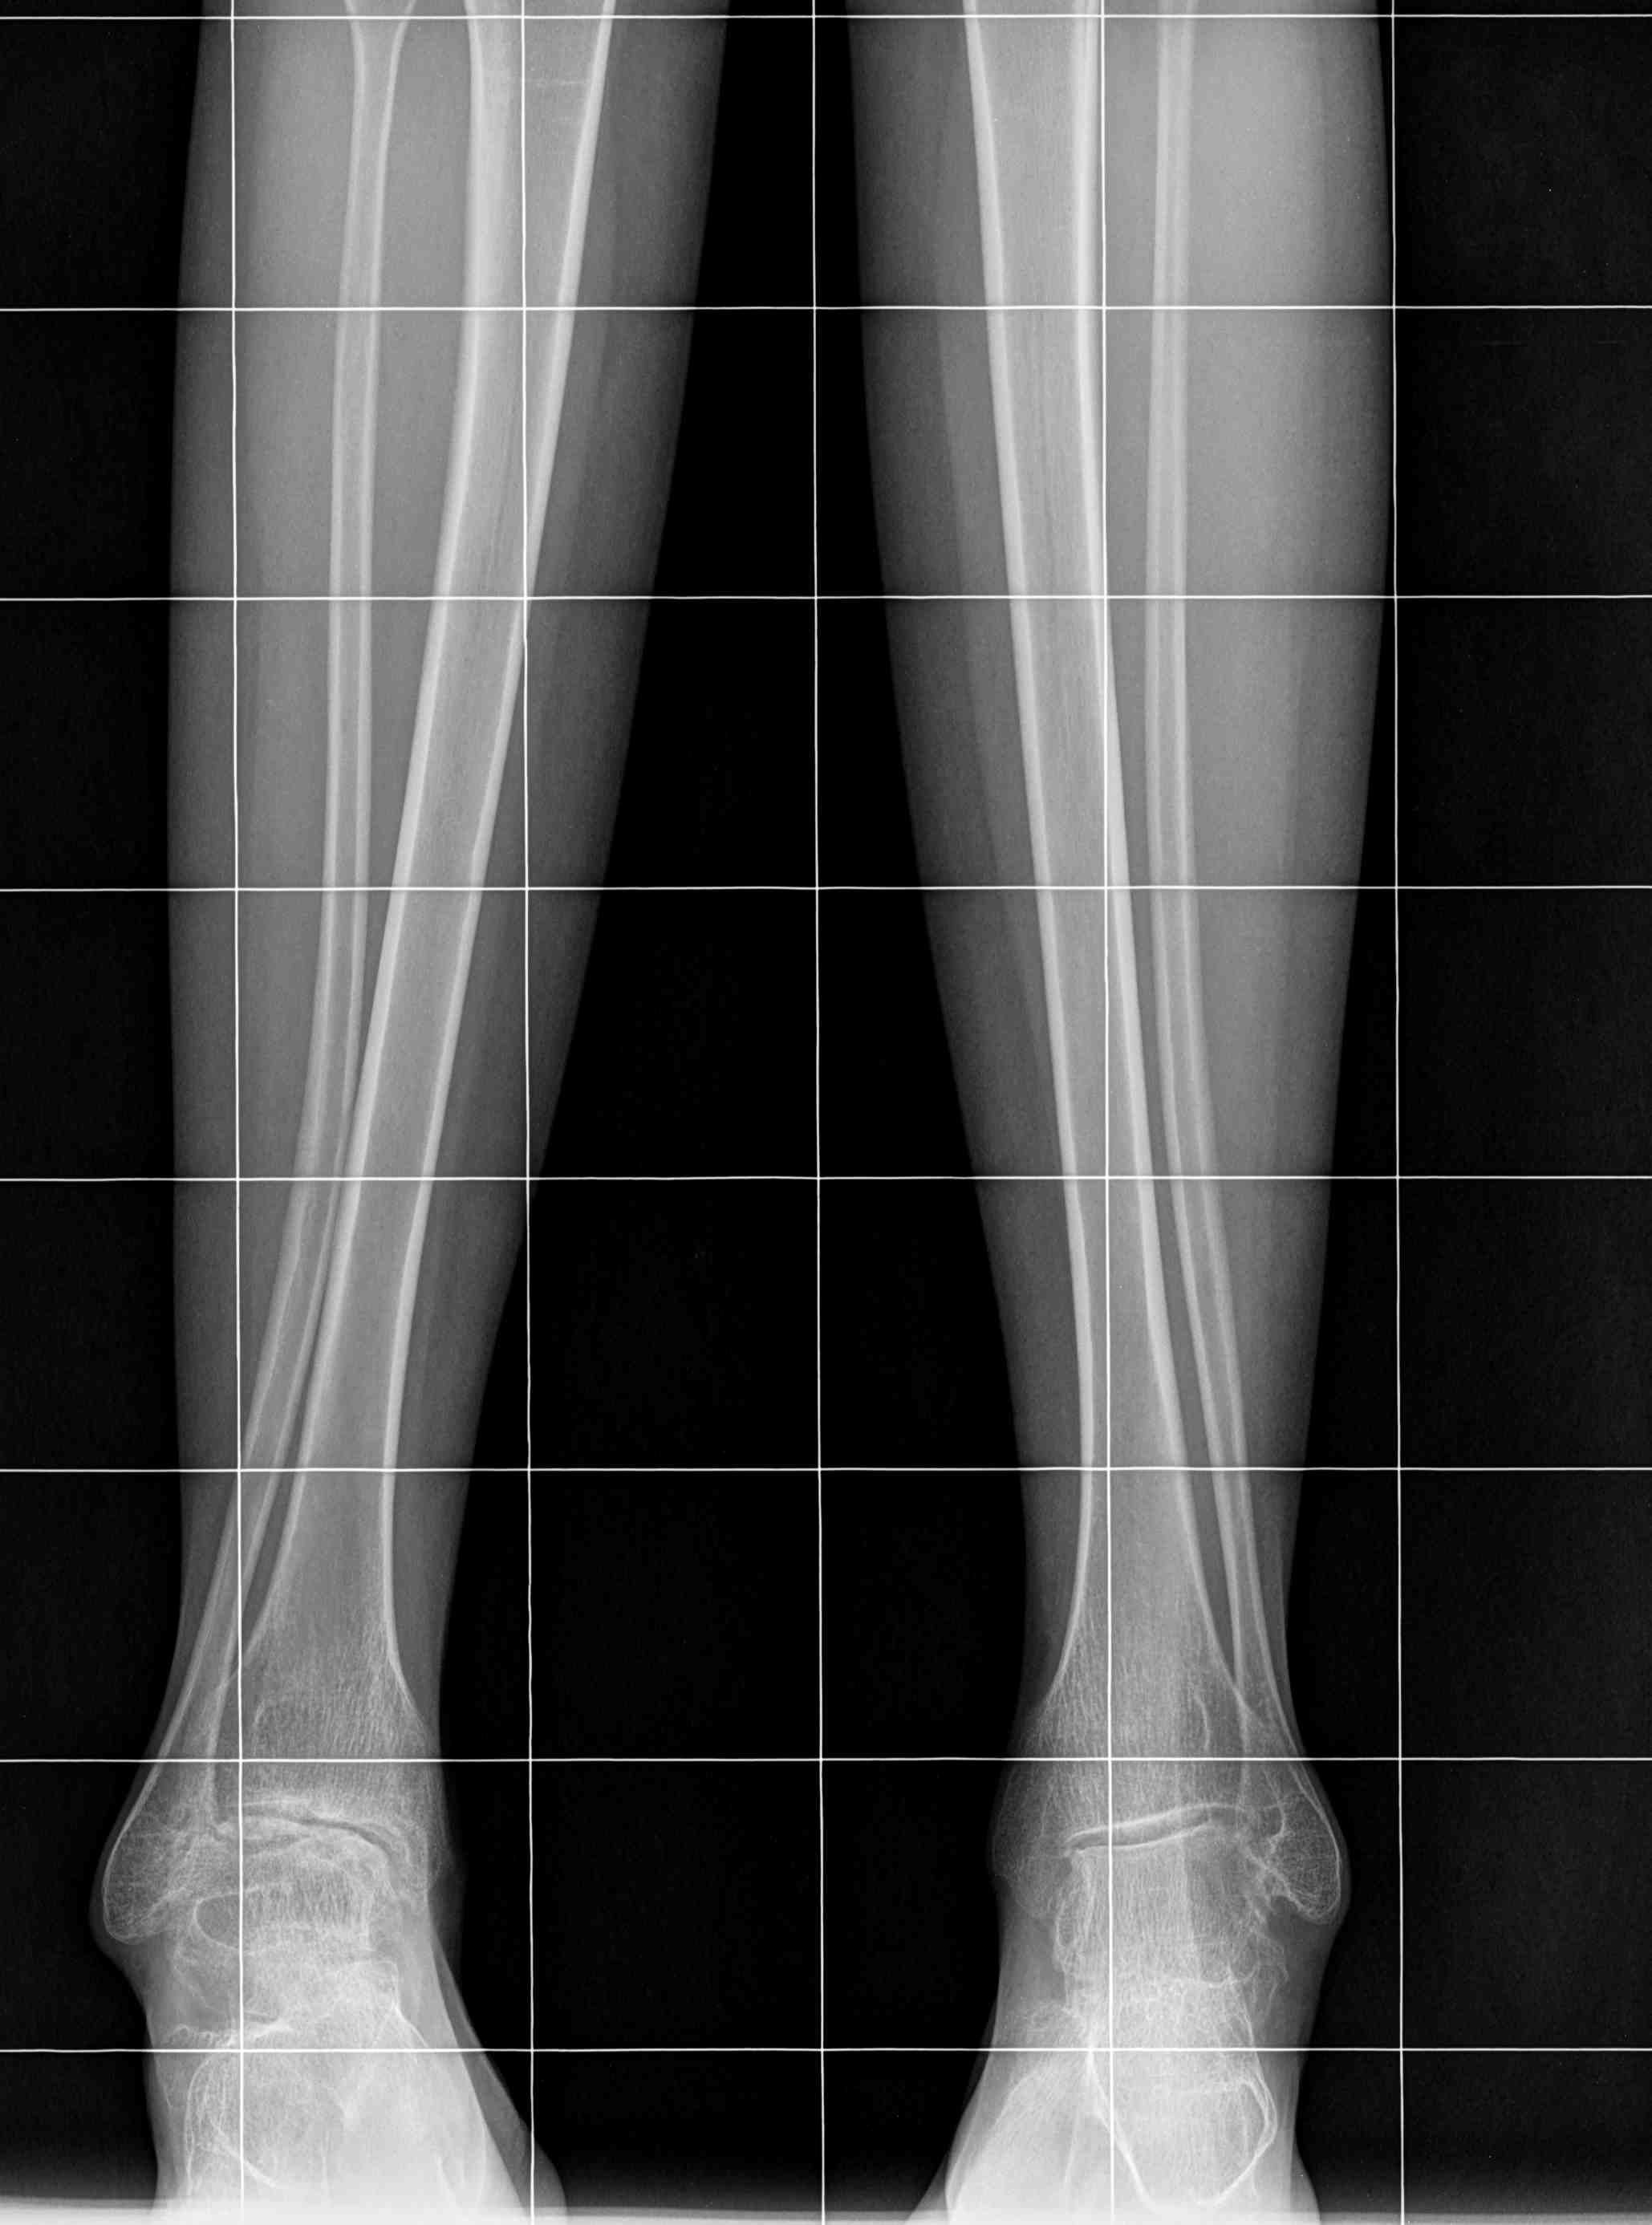

Имя     : GORODENSKAYA E-S-- 14-08-1987- CR from 17-02-2016 3 S2 I0	(2).jpg

Тип     : image/jpeg

Размер  : 144156 байтов

Описание: отсутствует

Url     : http://weborto.net:8080/pipermail/ortho/attachments/20160920/04b75196/attachment-0008.jpg